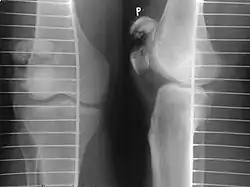

The patella can break in various ways depending on the way it is injured, and into two or more pieces.[1] Types include transverse, the most common, with one fracture line;[5] marginal; osteochondral; and the rare vertical type, or stellate, where a direct compression force gives rise to a comminuted pattern.[5][7] Patella fractures can be further classified as displaced, where the broken ends of bone do not line up correctly and separate by more than 2mm, or undisplaced and stable where pieces of bone remain in contact with each other.[1][7] If fragments of patella bone stick out from the skin it is known as an open patella fracture, and closed if the overlying skin is intact.[1]

Transverse fracture of patella -

Comminuted fracture of patella -

Osteochondral fracture of patella -

Vertical patella fracture